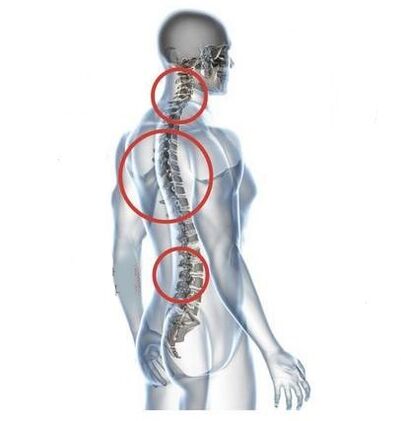

Garapenaren hasierako fasean, osteokondrosia asintomatikoa da. Burua makurtuta edo jarduera fisiko biziarekin egonaldi luze baten ondoren, ondoeza arina gertatzen da lepoaren atzealdean. Gaixoak ez du presarik medikua ikusteko, muskulu-tentsioaren ondorioekin nahastuz. Patologia poliki-poliki baina etengabe aurrera doa.

Lepoko ondoeza, pixkanaka, lepoko minak eta minak ordezkatzen dira, altxatze pisutsuak, hipotermia edo eguraldi aldaketaren ondoren areagotuz. Trápaga osteokondrosiaren beste sintoma zehatz batzuk agertzen dira:

- kurrinkatzea, burua okertzean edo biratzean klik egitean;

- mugikortasun mugatua bizkarrezurra zerbikalean;

- mina zorrotz eta larria areagotzeetan.

Orno arteko diskoak eta ornoak deformatu ahala, gaixoaren egoerak okerrera egiten du. Osteokondrosiaren ibilbidea osteofitoek eragindako konpresioak edo bizkarrezurreko sustraien eta orno-arteriaren irtengune hernialaren ondoriozko sintoma neurogenikoek zaildu egiten dute. Buruko minak, zorabioak, odol-presioaren aldaketak agertzen dira eta ikusmen- eta entzumen-zorroztasuna gutxitzen dira.